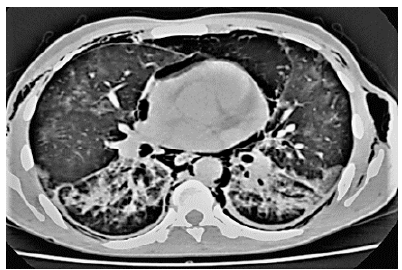

Bizarre Presentation of Huge Primary Pulmonary Leiomyoma